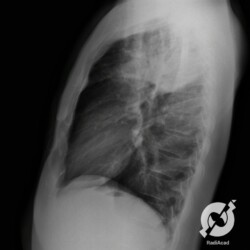

E o nome dado a esta alteração radiográfica que corresponde à substituição do ar alveolar por líquido é a consolidação alveolar.

Uma consolidação alveolar é, por definição, uma opacidade (imagem densa, branquinha) homogênea ou às vezes heterogênea (pela presença de calcificações ou cavidades), de limites mal definidos, exceto quando toca a pleura da parede ou das cissuras pulmonares. É um termo usado tanto em radiografia, como em tomografia computadorizada. Na tomografia, um outro termo é usado: vidro fosco, que é uma opacidade (branquinha mas não tanto como a consolidação), que borra o pulmão mas deixa ver os vasos de permeio (igual bigode de adolescente: dá pra ver todo o fundo).

Nós vamos mostrar aqui um pequeno apanhado de pneumonias de variados agentes, em diversos segmentos e lobos pulmonares, com extensões variadas. O objetivo é identificar o padrão radiológico de consolidação alveolar e não determinar o agente infeccioso, isso vai ser assunto para mais adiante. Aliás já antecipo que é fundamental saber localizar a lesão, porque alguns destes bichos gostam de determinados segmentos, alguns tumores também têm as suas preferências, então localização é fundamental. Se localização não fosse importante, um apartamento na beira do mar sairia o mesmo preço de um apartamento de frente pra BR-101, concordam?

Seguem alguns dos nossos casos de pneumonia para vocês treinarem os olhos e não se apavorarem nos plantões.